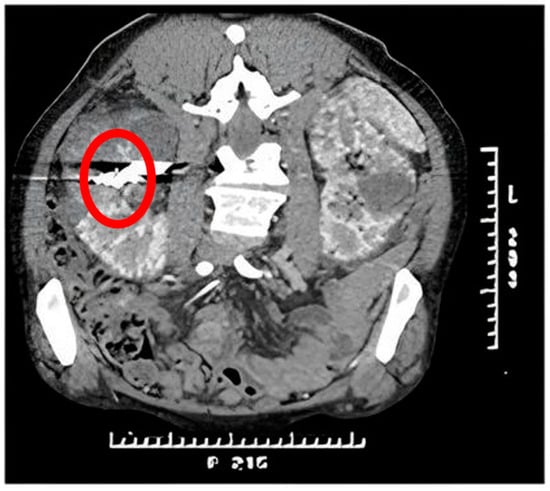

Appendix A.2. Clinical Case 2: Treatment of Endoleak Type II Inferior Mesenteric Artery